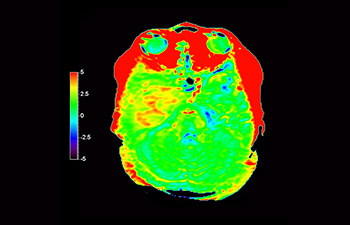

Astrocytome du cerveau, post-radiothérapie

avec 3D APT